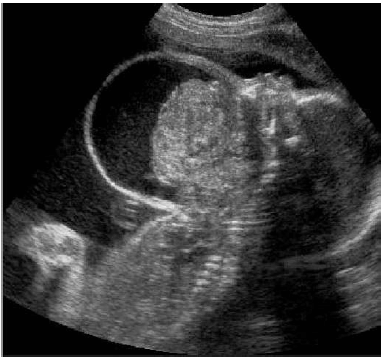

Considerando a imagem acima, assinale a alternativa que apresenta uma alteração ultrassonográfica que pode se associar aos teratomas cervicais.